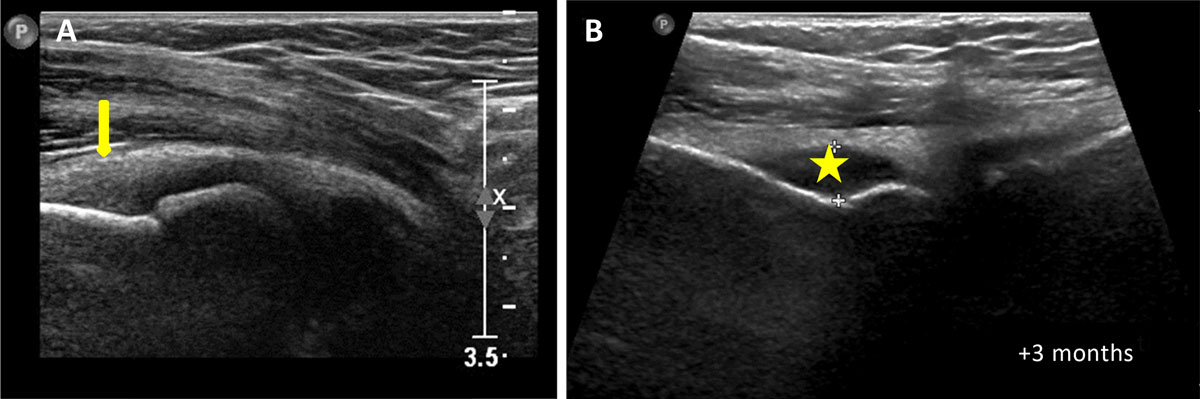

A 9-year-old boy presented to the rheumatology consultation with left elbow pain for the prior three months. The pain was associated with swelling, stiffness, and limitation of movement suggestive of inflammation. The blood work was normal. Mono-articular juvenile idiopathic arthritis (JIA) was suspected, and the patient was referred for left elbow ultrasound, which confirmed synovial thickening (arrow on Figure 1A). Treatment with nonsteroidal anti-inflammatory drugs was started, and three weeks later an intra-articular infiltration with cortico-steroids was carried out.

Figure 1

Three months later, as the symptoms persisted, a new ultrasound of the elbow was performed, demonstrating joint effusion (asterisk on Figure 1B); elbow radiograph on the same day showed metaphyseal sclerosis (blue asterisk on Figure 2A), peri-articular osteopenia (green asterisk on Figure 2A) and periosteal apposition (arrows on Figure 2A). Septic arthritis was suspected and a joint lavage was performed; bacteriological samples were negative. Treatment with ledertrexate for chronic synovitis was started.